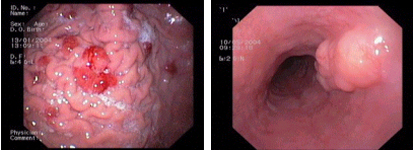

imagen4

Fundic gland hyperplasia in the stomach, a common benign condition